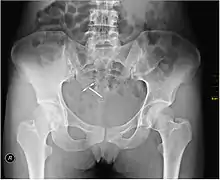

An intrauterine device (IUD), also known as intrauterine contraceptive device (IUCD or ICD) or coil,[3] is a small, often T-shaped birth control device that is inserted into the uterus to prevent pregnancy. IUDs are one form of long-acting reversible birth control (LARC).[4] One study found that female family planning providers choose LARC methods more often (41.7%) than the general public (12.1%).[5] Among birth control methods, IUDs, along with other contraceptive implants, result in the greatest satisfaction among users.[6]

IUDs are safe and effective in adolescents as well as those who have not previously had children.[6][7] Once an IUD is removed, even after long-term use, fertility returns to normal rapidly.[8] Copper devices have a failure rate of about 0.8% while hormonal (levonorgestrel) devices fail about 0.2% of the time within the first year of use.[9] In comparison, male sterilization and male condoms have a failure rate of about 0.15% and 15%, respectively.[10] Copper IUDs can also be used as emergency contraception within five days of unprotected sex.[11]

Although copper IUDs may increase menstrual bleeding and result in painful cramps,[12] hormonal IUDs may reduce menstrual bleeding or stop menstruation altogether.[13] However, women can have daily spotting for several months and it can take up to three months for there to be a 90% decrease in bleeding with hormonal IUDs.[14] Cramping can be treated with NSAIDs.[15] More serious potential complications include expulsion (2–5%) and rarely perforation of the uterus (less than 0.7%).[13][15] IUDs do not affect breastfeeding and can be inserted immediately after delivery.[13] They may also be used immediately after an abortion.[16][17]